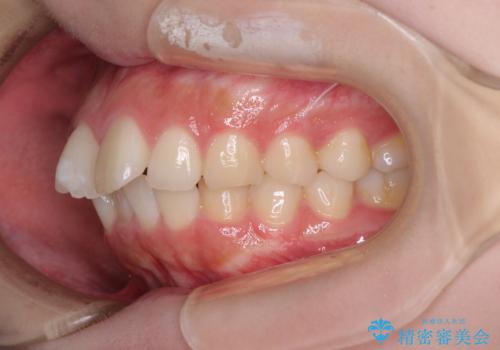

前歯のデコボコをインビザラインできれいに整える

- 前歯のデコボコと上下の隙間を気にして来院された患者様です。

前歯の捻れを改善するとともに、口元が少しでも引っ込むように治療計画を立て、仕上げることができました。